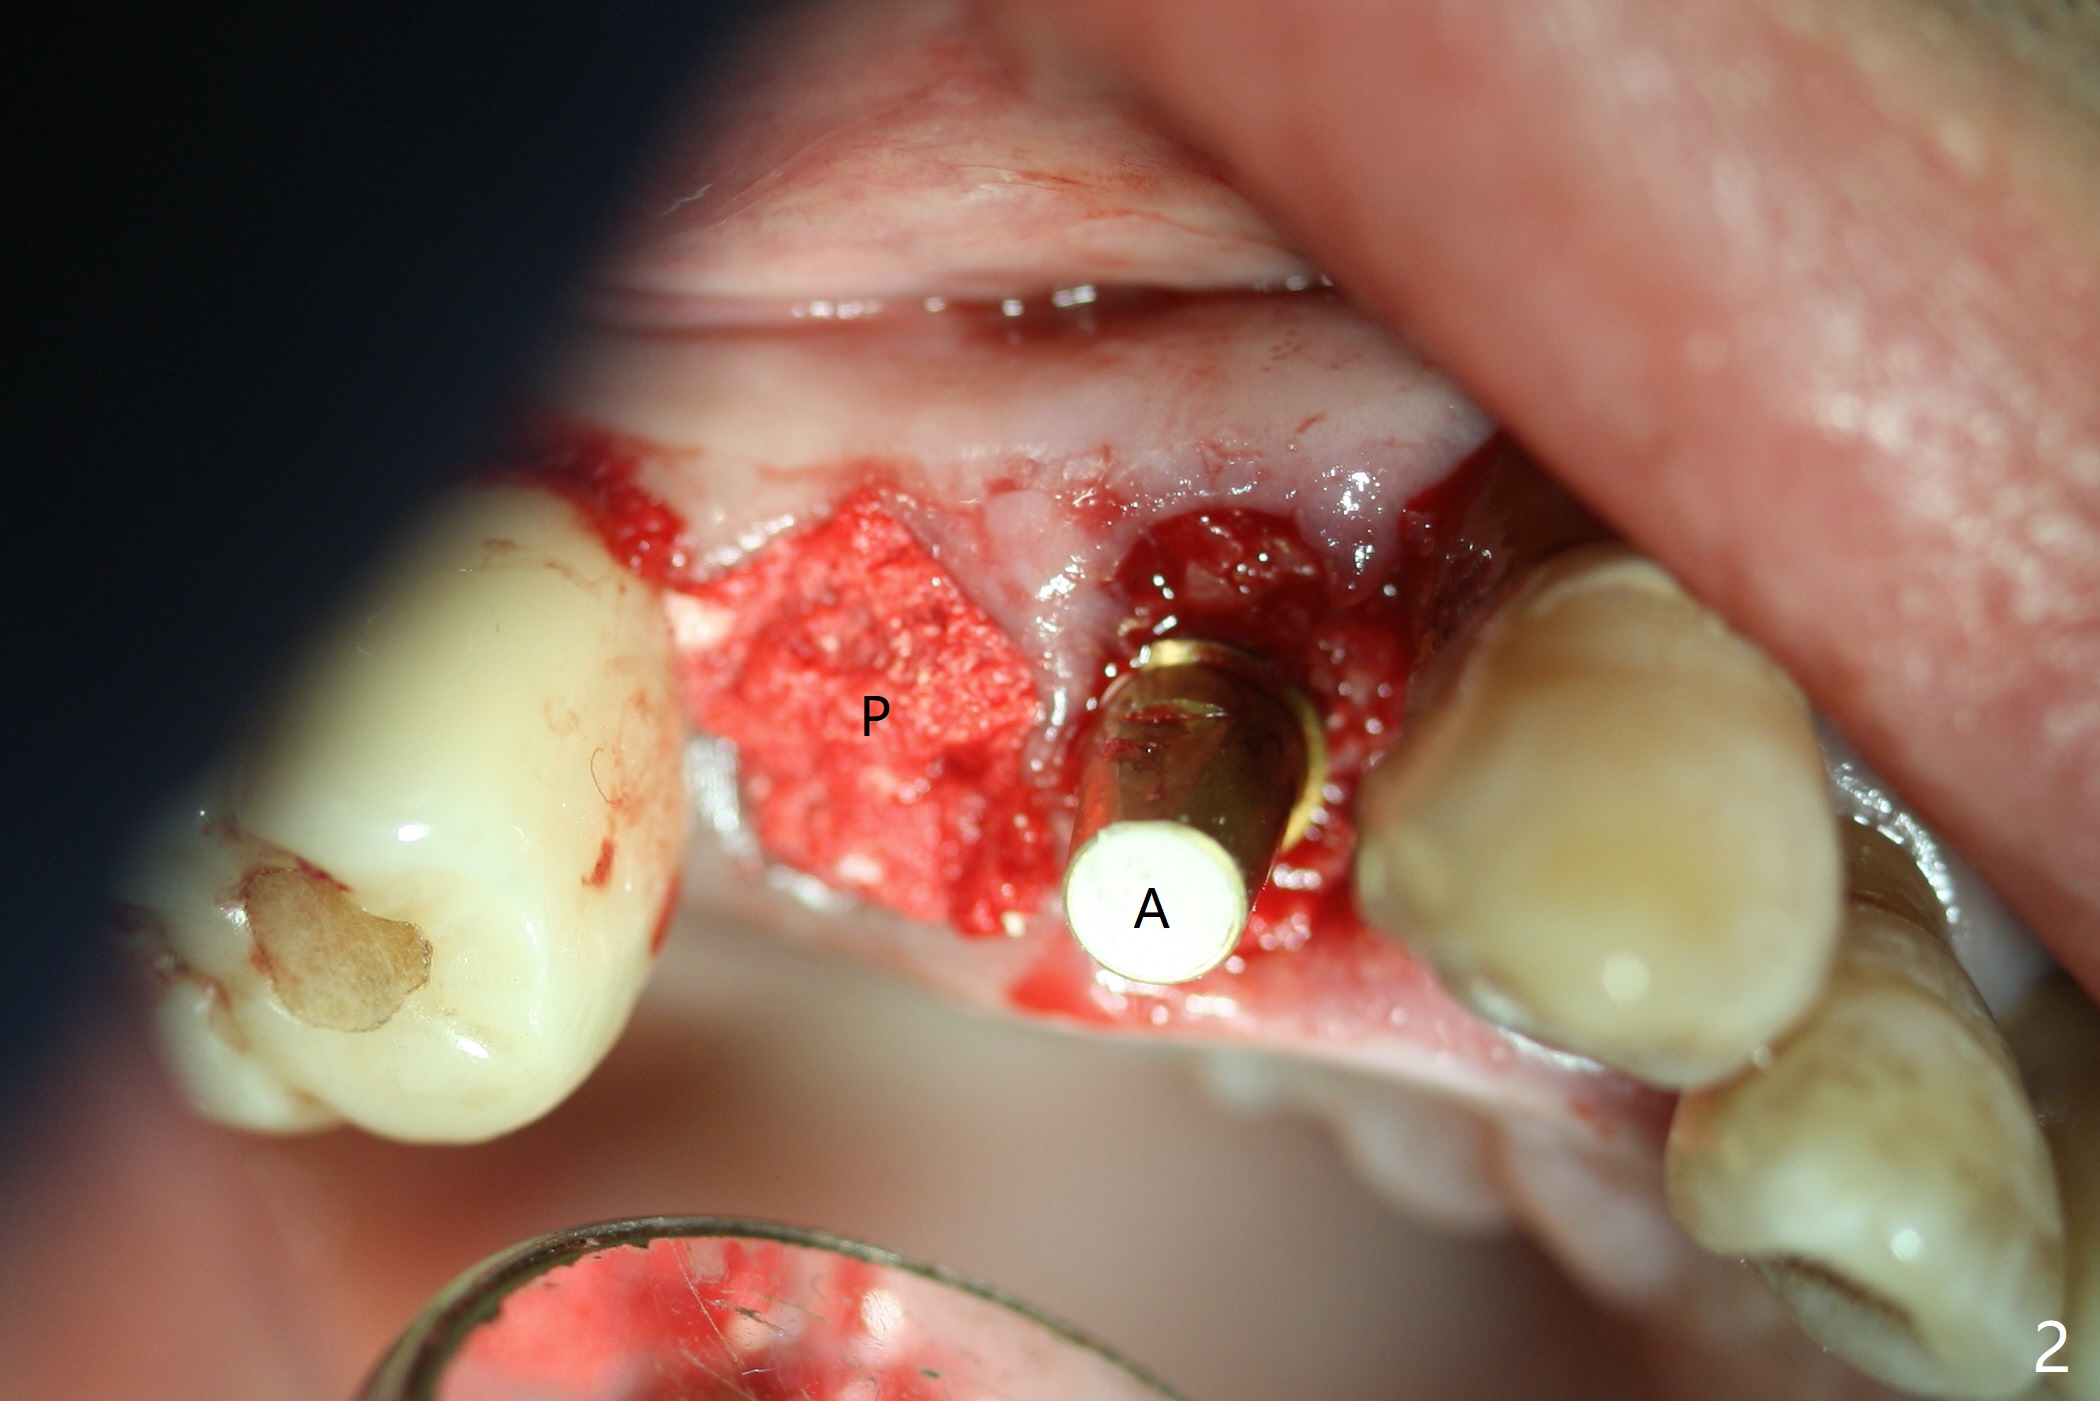

Today schedule is to extract the teeth #4 and 5 and place an implant at #5. When the latter is done, it appears that the implant at #15 should be placed at the same appointment (Fig.1). Once an abutment is placed at #5 (Fig.2 A, 5) for temporary crown (Fig.4 T) , the guide may be not seated again unless the crown is removed. Luckily the implant placement at #15 is quick and smooth with the guide (Fig.3,6). The implants seem to be covered by the bone 4 months postop (Fig.7,8). #15 abutment screw needs retightening because of long crown 1.5 months post cementation. Access hole is palatal. There is premature contact in lateral movement. The buccolingual occlusal table is large at #14 and 15. In fact there is more occlusal contact at #14 than #15 in centric occlusion. Tissue level implants should have been placed to reduce implant/abutment loosening. The incomplete abutment seating (Fig.5,7) is noted after retightening the loose cantilever FPD 1 year post cementation (Fig.9 <). After removal of the FPD, the abutment is reseated completely without interference of the proximal contacts (Fig.10).